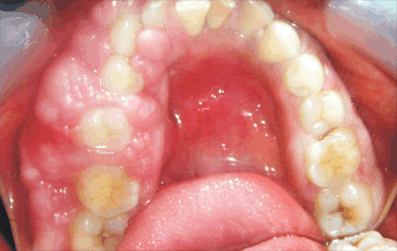

Hereditary Gingival Fibromatosis. (Page 3)